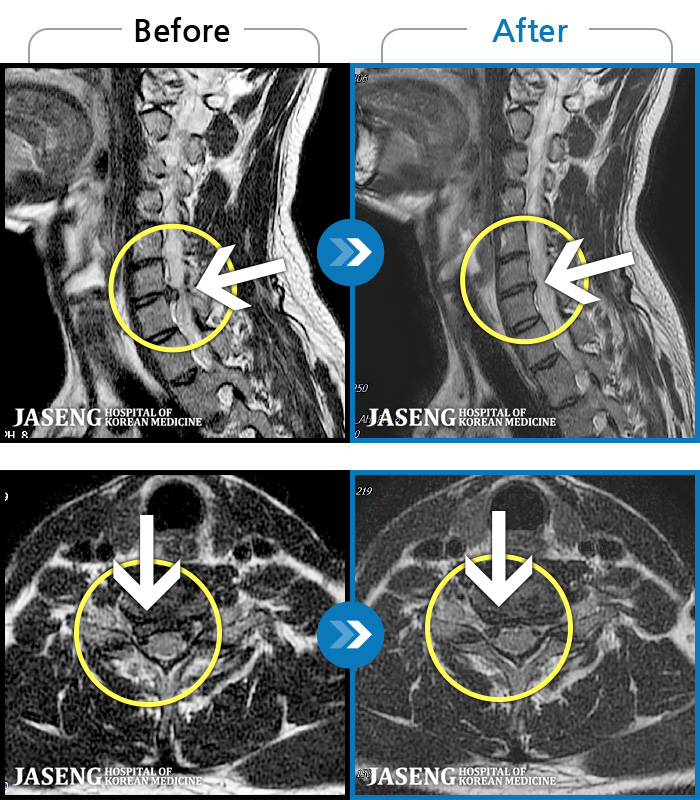

[] 03.04.01~09.11.01

ȯںп Ǹ ǿ ԿǾ, ο ġ ۿ Ƿ ġḦ Ͻñ ٶϴ.